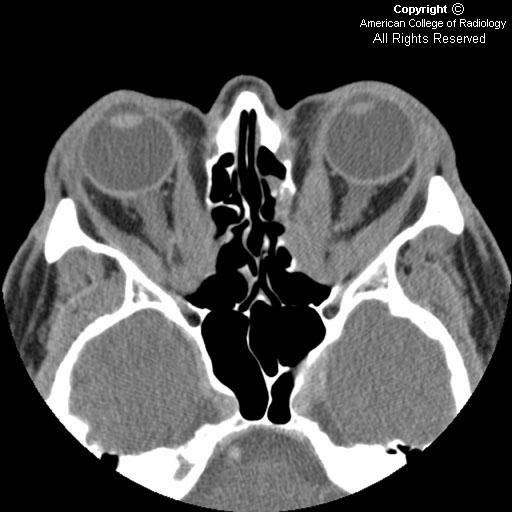

Neuroradiology On the Net Graves ophthalmopathy Graves Disease Ophthalmology learn about the symptoms, causes and treatments of ted, an autoimmune condition that affects the eyes. thyroid eye disease (ted) is an autoimmune condition resulting in inflammation and swelling of the extraocular muscles, fatty tissue and connective tissue within the orbit. Find out how to prevent. learn about the symptoms, causes, diagnosis and treatment of graves’ eye. Graves Disease Ophthalmology.